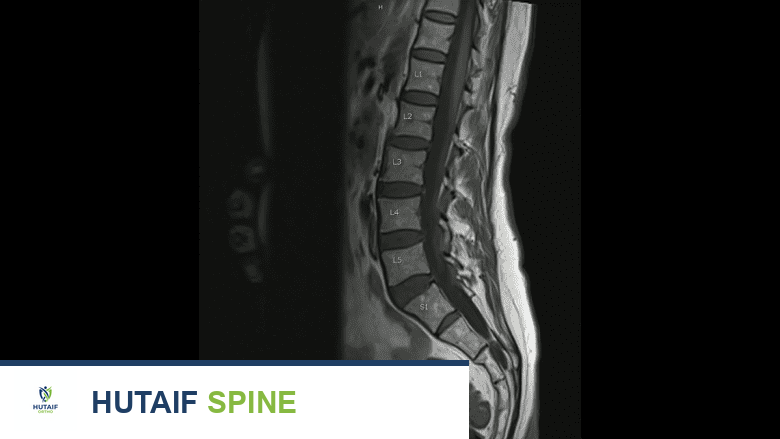

يوفر التصوير بالرنين المغناطيسي رؤية مفصلة لأنسجة الفقرات القطنية أثناء تشخيص تنكس القرص.

التصوير بالرنين المغناطيسي (MRI)

يُعدّ التصوير بالرنين المغناطيسي (MRI) الأداة الأكثر فعالية وحساسية لتشخيص مرض القرص التنكسي القطني وتحديد مدى تأثيره على الهياكل المحيطة. قد يتطلب التشخيص النهائي لمرض القرص التنكسي القطني إجراء فحص بالرنين المغناطيسي للتأكد من أن مشكلات أخرى، مثل الكسر أو الانزلاق الغضروفي، لا تساهم في الألم. إذا كانت هناك حاجة إلى الجراحة، فإن فحص التصوير ضروري قبل الإجراء لتحديد مكان القرص المتنكس بدقة والتخطيط للجراحة.

كيف يعمل الرنين المغناطيسي؟

يستخدم فحص الرنين المغناطيسي (MRI) مغناطيسًا عالي الطاقة لمواءمة واكتشاف جزيئات الماء في الجسم، مما يسمح للأطباء بتصوير الأنسجة الرخوة مثل العضلات والأربطة والأوتار والأقراص الفقرية. تعتمد فحوصات الرنين المغناطيسي على المغناطيسية بدلاً من الإشعاع – المستخدم في الأشعة السينية و الأشعة المقطعية – لذلك هناك مخاطر قليلة مرتبطة بفحص الرنين المغناطيسي، والفحوصات ليست مؤلمة.

المعلومات التي يوفرها الرنين المغناطيسي:

يمكن أن توفر فحوصات الرنين المغناطيسي معلومات مفيدة بشأن:

- ارتفاع القرص: يظهر فقدان ارتفاع القرص بوضوح.

- شكل القرص: يكشف عن أي انتفاخات أو انزلاقات غضروفية.

- تآكل الصفائح النهائية: يظهر التغيرات في أسطح الفقرات المجاورة للقرص.

- انضغاط الأعصاب: يوضح ما إذا كانت الأعصاب الشوكية مضغوطة بواسطة القرص المتنكس أو النتوءات العظمية.

- ترطيب القرص: يُعدّ هذا مؤشرًا حيويًا على صحة القرص. إذا كان هناك القليل من الترطيب أو عدم وجوده، فقد يُشار إليه على أنه "قرص أسود" (black disc)، حيث سيظهر القرص باللون الأسود في فحص الرنين المغناطيسي بدلاً من اللون الفاتح الذي يشير إلى محتوى مائي جيد.

- استبعاد حالات أخرى: يساعد في استبعاد أسباب أخرى للألم مثل الأورام، الالتهابات، أو الكسور.